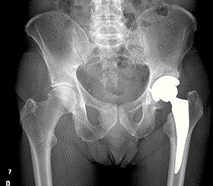

For neck of femur fractures, open reduction and internal fixation are indicated for most physiologically young patients.

Undisplaced fractures are treated with cannulated screws or a sliding hip screw. Arthroplasty is indicated for elderly patients with displaced fractures.